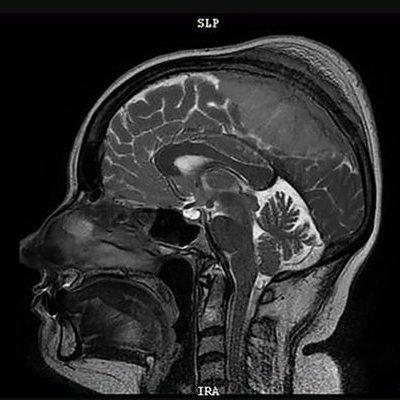

Ученые Института цитологии РАН обнаружили, что метод лечения нейродегенеративных заболеваний, таких как болезнь Паркинсона и Альцгеймера, заключающийся в медикаментозном разрушении амилоидных бляшек, может ускорять разрушение тканей мозга.

Продукты деградации амилоидов часто оказываются токсичнее исходных образований, что способствует образованию новых патологических фибрилл и их распространению между клетками.